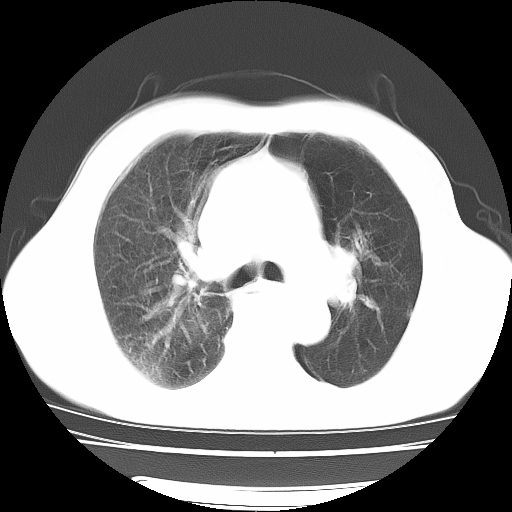

男,71岁,咳嗽,气喘10年,再发并咯血.胸片见气胸

考虑  左肺中心型肺癌伴阻塞性肺炎,肺不张,纵膈淋巴结肿大。慢支炎,肺气肿,左侧气胸肺压缩5%

左侧中央型肺癌伴纵膈淋巴结转移。

左肺中心型肺癌伴阻塞性肺炎,肺不张,纵膈淋巴结肿大

1)考虑左肺中心型肺癌伴阻塞性肺炎、左肺下叶肺不张、左侧肺气肿,纵膈淋巴结转移。2)左侧气胸(肺组织压缩约5%)。

左肺中心型肺癌伴阻塞性肺不张、肺气肿 。

1)考虑左肺中心型肺癌伴阻塞性肺炎、左肺下叶肺不张、左侧肺气肿,纵膈淋巴结转移。2)左侧气胸。